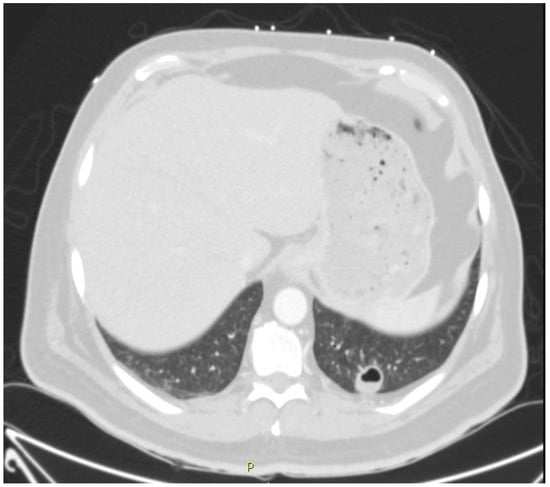

3.2. Pulmonary Manifestations of Coccidioidomycosis and in This Patient